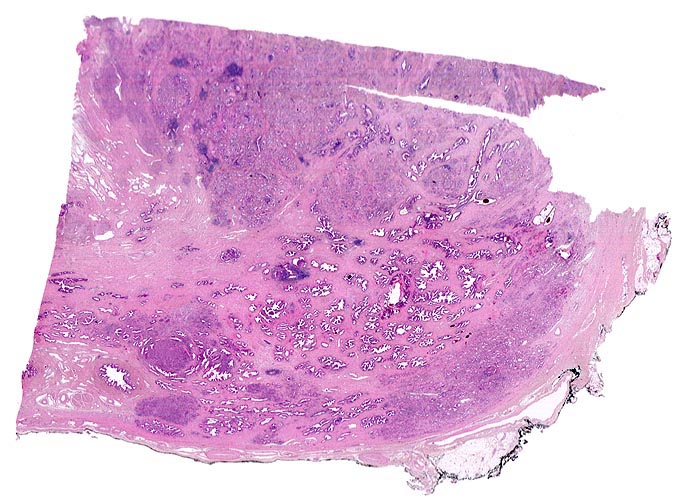

Adenokarzinom der Prostata

Multiple Karzinomherde infiltrieren das Prostatagewebe. Die normalen Drüsen sind deutlich grösser als die Karzinomdrüsen und enthalten in der Übersichtsvergrösserung erkennbare Lumina. Da die Karzinomdrüsen deutlich kleiner sind, erscheinen die Karzinomherde in der schwachen Vergrösserung als dunkle, unscharf begrenzte Flecken ohne erkennbare drüsige Strukturen.

Der Resektionsrand ist mit schwarzer Tusche markiert (schwarzer Streifen am Rand des Präparates).